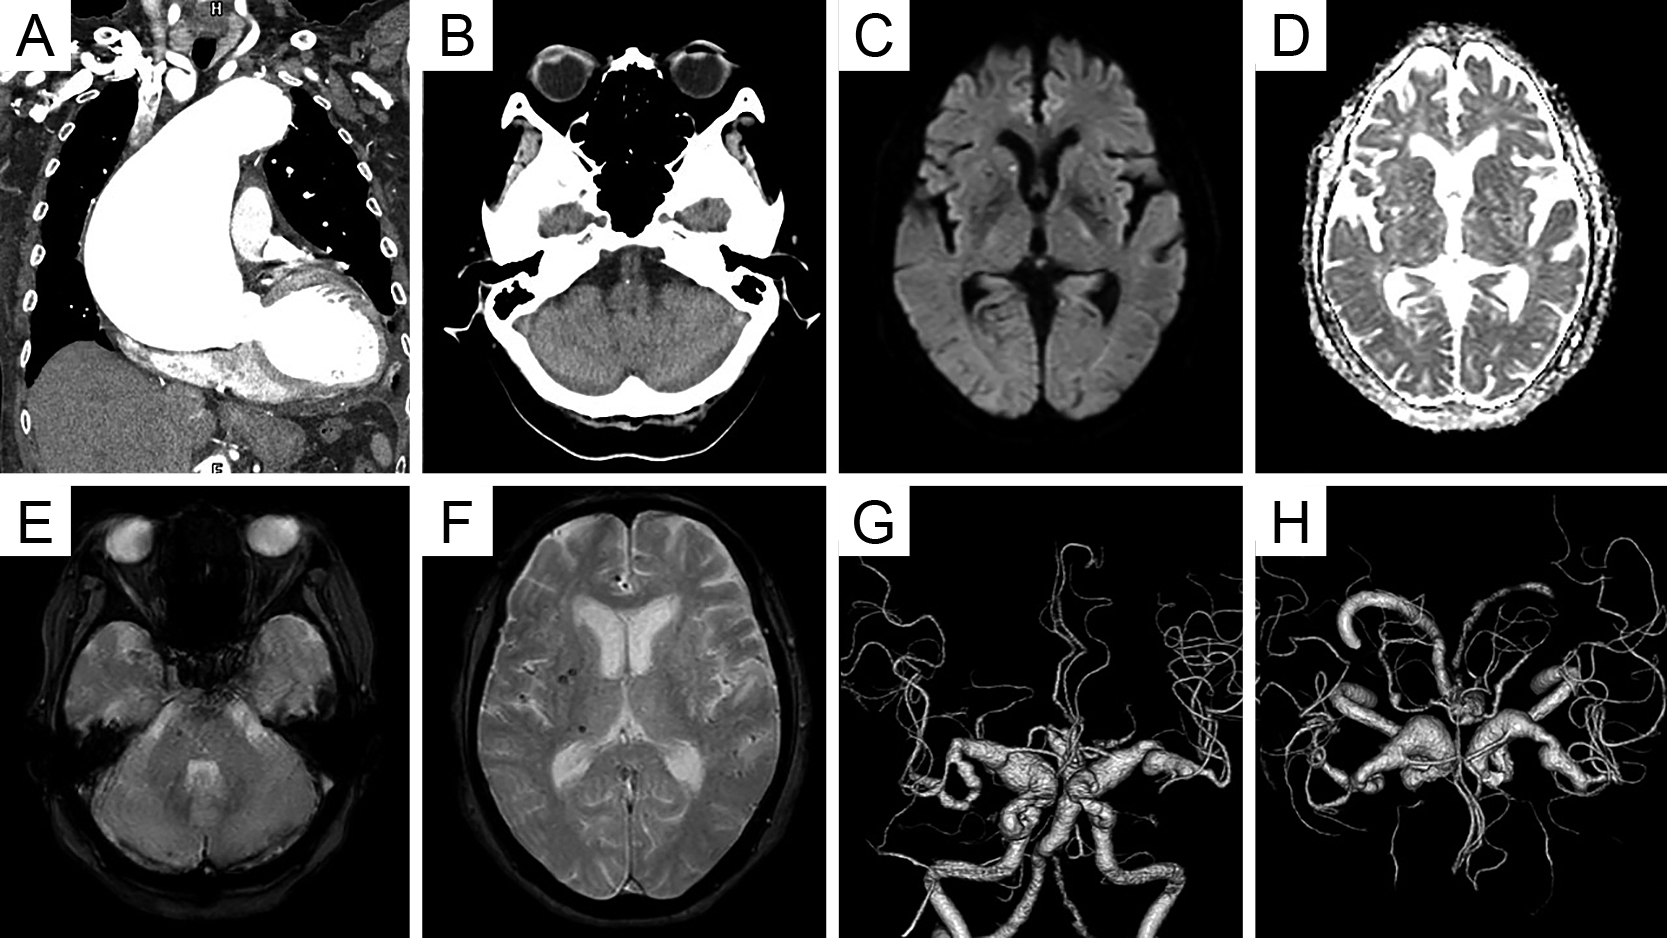

直接経口抗凝固薬内服にもかかわらず脳梗塞を発症した心房細動患者に対する経皮的左心耳閉鎖術:症例報告

Percutaneous left atrial appendage closure for atrial fibrillation-related ischemic stroke despite direct oral anticoagulation: a case report

川端 健新, 江頭 柊平, 村松 恭祐, 逸見 文昭, 宇羽野 恵, 小西 明範, 大森 奈美, 山口 徹雄, 児玉 隆秀, 上坂 義和

Kenshin Kawabata, Shuhei Egashira, Kyosuke Muramatsu, Fumiaki Henmi, Megumi Ubano, Akinori Konishi, Nami Omori, Tetsuo Yamaguchi, Takahide Kodama, Yoshikazu Uesaka

2026/02/13